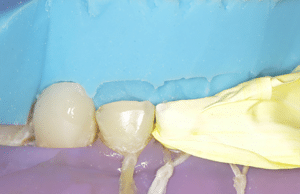

Le laboratoire nous envoie un modèle imprimé du wax-up palatin (Fig.14a, b, c). On va thermoformer dessus une gouttière transparente rigide. Cette gouttière est rebasée sur le modèle à l’aide de silicone transparent du type Exaclear (GC).

Fig.14a, b, c : Composites palatins directs.

Fig.14b.

Fig.14c.

On isole les dents maxillaires. Avec la technique de « pressée », la digue peut gêner la mise en place de la gouttière. Il faut toujours penser à l’essayer avant de charger le composite à l’intérieur. Si la pose de la digue n’est pas possible, on cherchera à isoler au mieux : écarteurs de bouche, cordonnet de téflon dans le sulcus et aspiration. Ensuite on met en place le système adhésif. On travaille les dents une par une, ou une dent sur deux. Pour ne pas coller les dents entre elles, on positionnera du téflon sur les dents adjacentes à la dent qui va être restaurée.

Une fois l’adhésif polymérisé, on place du composite de restauration chauffé (donc plus mou) dans la gouttière et on presse cette gouttière sur les dents. Après photopolymérisation, la gouttière est retirée, les excès nettoyés et on passe à la dent suivante. L’avantage de cette technique est la gestion aisée de la morphologie et donc de l’occlusion. Elle reproduit presque fidèlement le wax-up du laboratoire. Mais il y a deux inconvénients : le premier est qu’on ne peut pas presser plus de 2 mm de composite en une seule couche (épaisseur maximale pour une photopolymérisation efficace). Si on doit restaurer plus de 2 mm, il faut faire un premier apport sans la gouttière puis presser la dernière couche à l’aide de la gouttière. Le premier apport peut légèrement dévier la gouttière sans que l’on s’en rende compte, faussant ainsi la reproduction de l’anatomie palatine. Le deuxième inconvénient est l’état de surface. Le silicone de rebasage fait beaucoup de micro-bulles et l’état de surface après retrait de la gouttière n’est pas aussi beau que celui d’un composite monté à la main. Il faut passer plus de temps sur le polissage.

Astuces

Pour que le silicone de rebasage tienne dans la gouttière, il faut percer à la fraise la face vestibulaire des dents (rétention mécanique) et mettre un adhésif à silicone (rétention chimique).